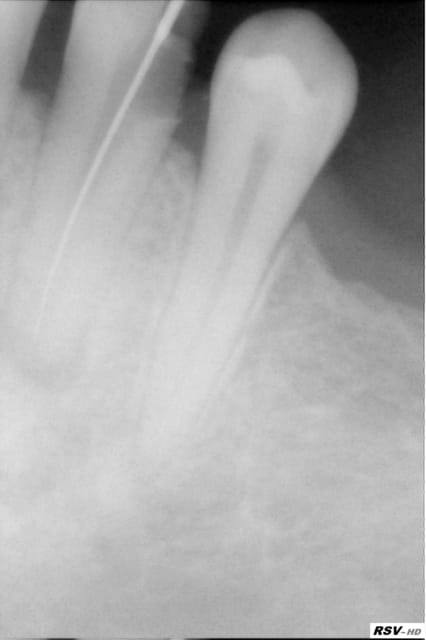

J’ai acheté récemment une RVG ‘’visiodent RSV HD’’, j’ai une radio ‘’GNATUS ‘’. En suivant le nombre de secondes indiquées sur le tableau de la radio qui est pour les adultes de:

0,08 pour les PM du bas, Incisifs et Canines haut et bas

0,10 pour les PM du haut et M du bas

0,12 pour les M du haut

J’obtiens des images un peu trop blanches, pas assez de contrastes, même en réajustant les contrastes sur le logiciel, ce n’est pas assez, je n arrive même pas a voir la limite de la dent !!!